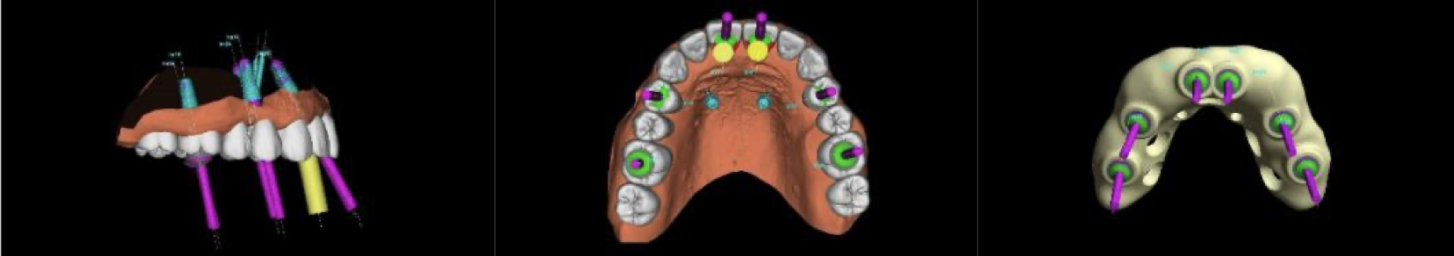

Для первичной операции был изготовлен индивидуальный хирургический шаблон (по которому хирург, как по навигатору, точно выполняет установку имплантатов), также до операции были изготовлены временные зубы, чтобы их можно было зафиксировать сразу после операции.

Хирургический шаблон – это компьютерное моделирование будущей позиции имплантата, с точностью до миллиметра. Далее по цифровой модели печатается пластиковый аналог, который и позиционируется во время операции во рту пациента.